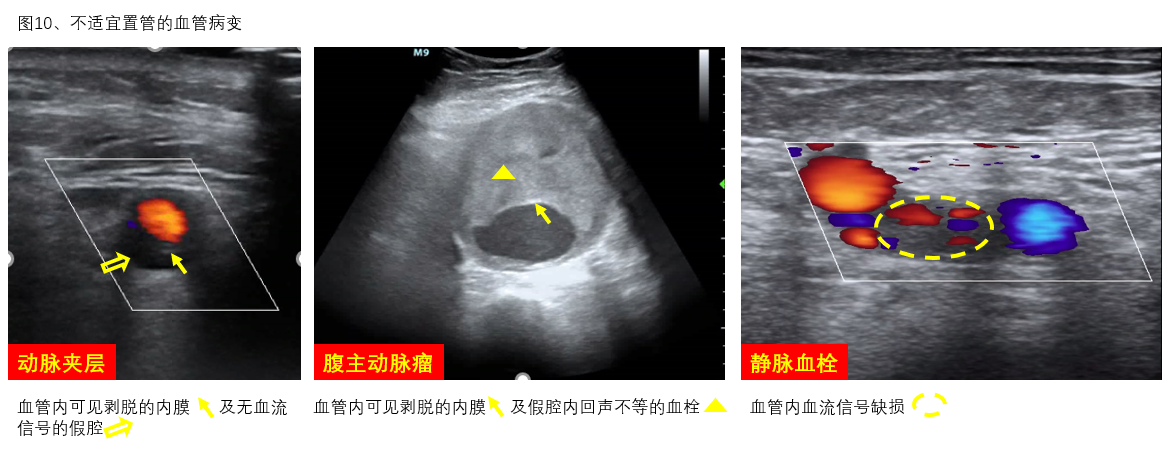

A、不宜穿刺情况:拟穿刺动脉穿刺部位及血液回流段血管有严重斑块、钙化、夹层、动脉瘤、动静脉瘘,穿刺点近心端管腔狭窄等(图10)。若双侧股动脉穿刺均不可行时,可选择右颈总、锁骨下、腋等其它动脉置管通路或中心置管途径进行ECMO支持。

图10